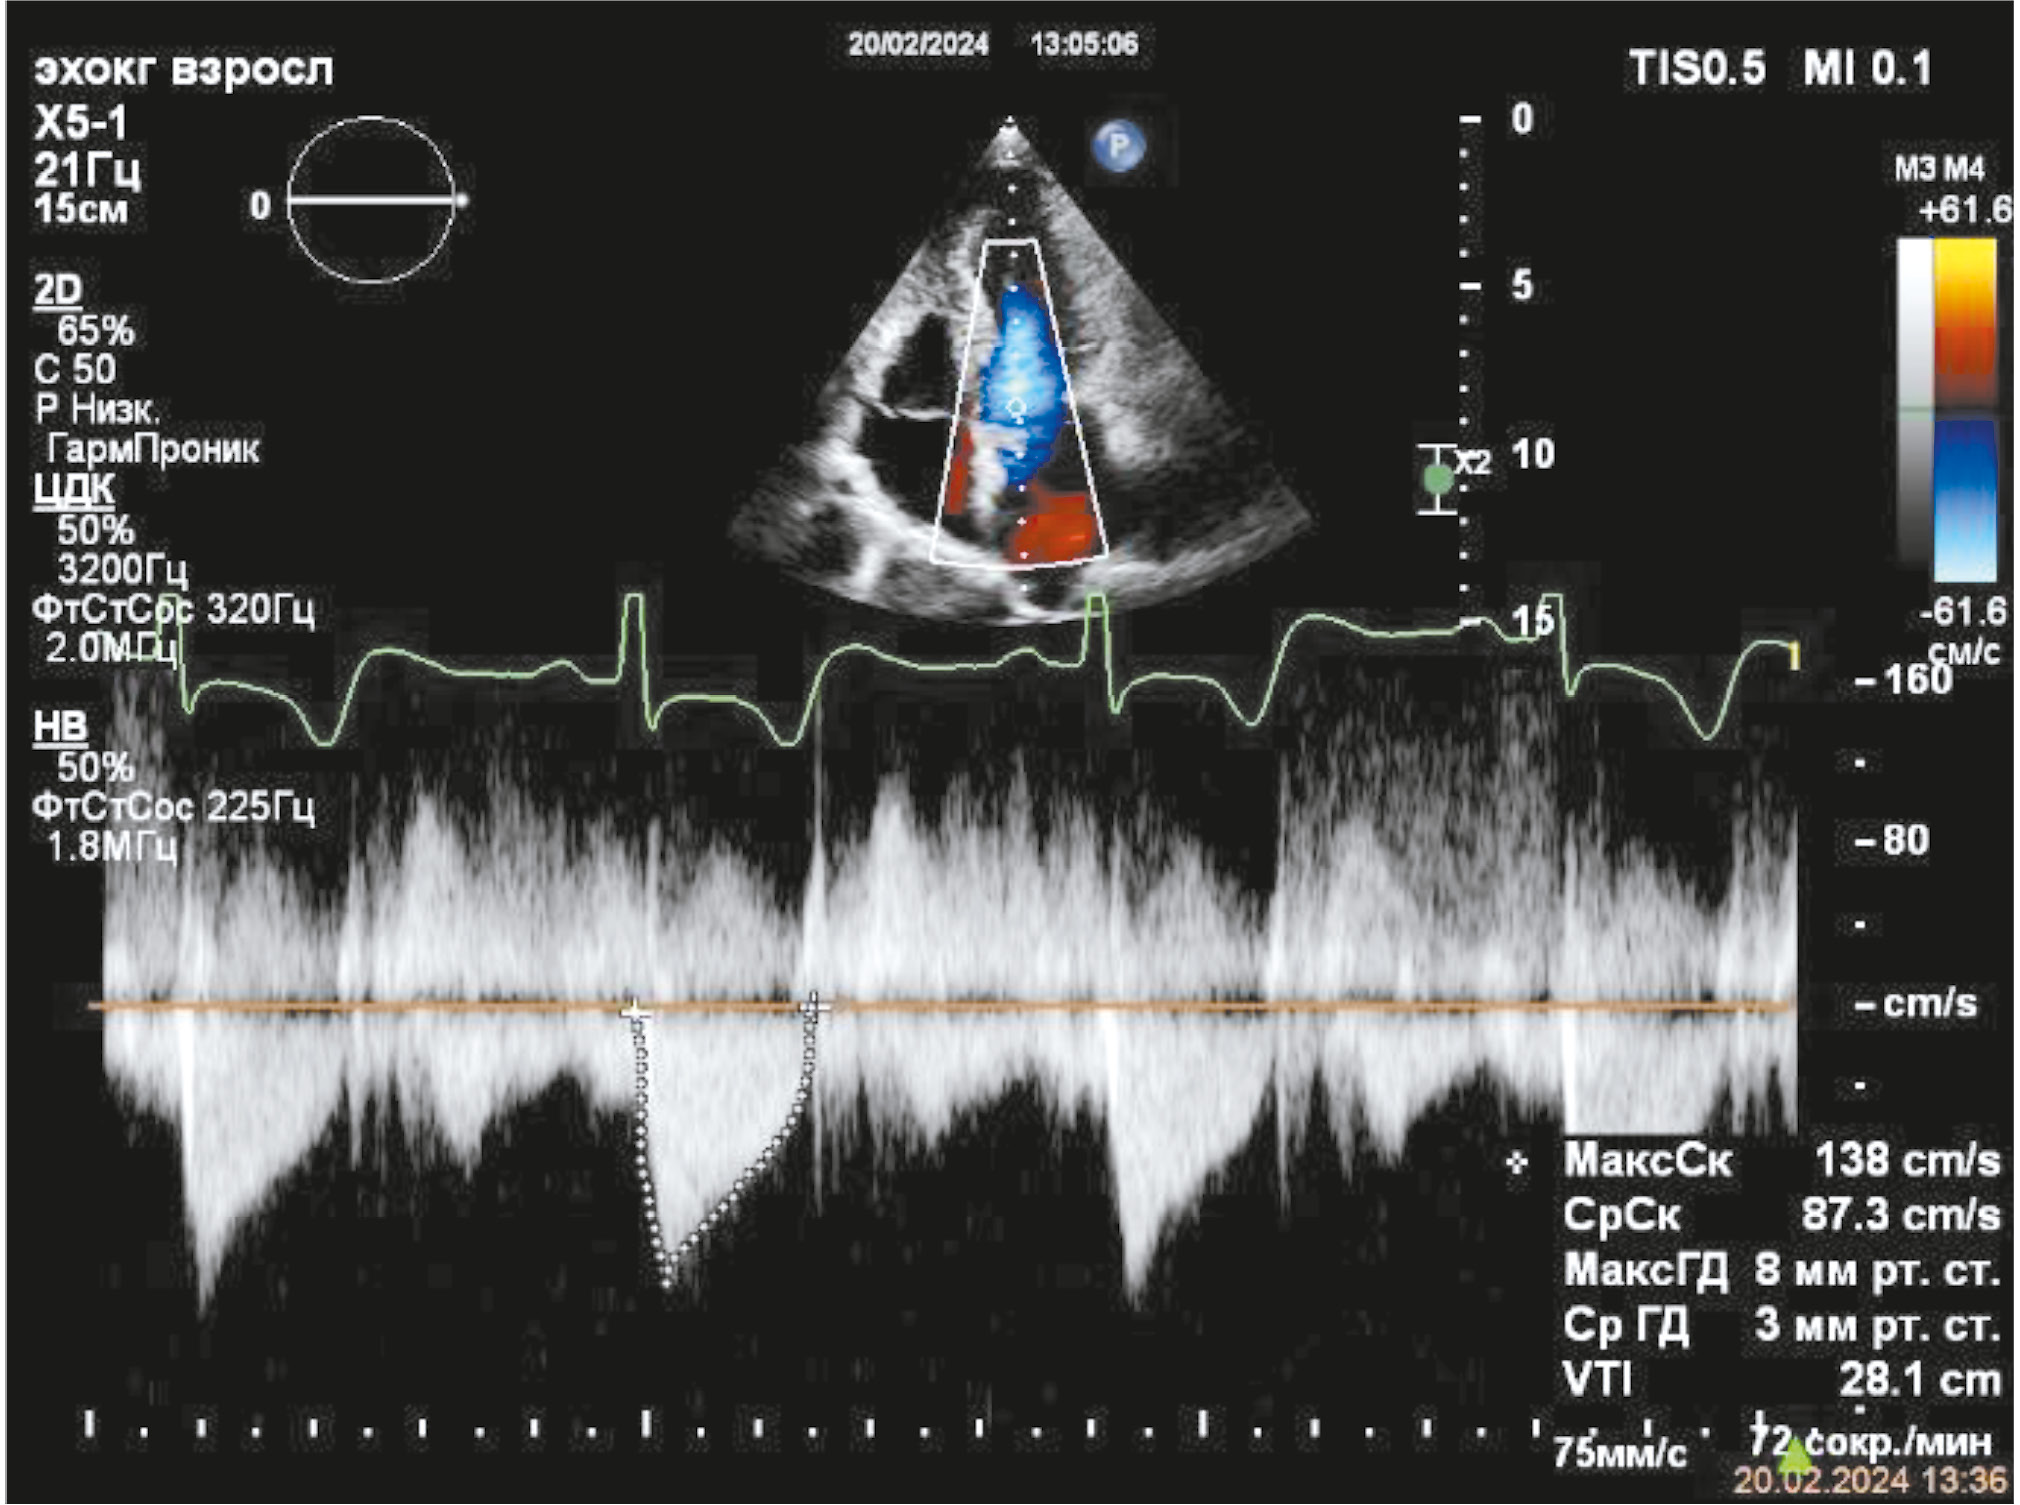

Учитывая несоответствие между клиническим состоянием пациентки и данными КАГ, была одномоментно выполнена вентрикулография: акинезия всех верхушечных сегментов ЛЖ. По окончании КАГ пациентка была направлена в отделение реанимации и интенсивной терапии для дальнейшего дообследования и интенсивной терапии. В день поступления была выполнена эхокардиография (ЭхоКГ): фракция выброса левого желудочка (ФВ ЛЖ) — 40%, толщина задней стенки (ЗС) ЛЖ — 17 мм, толщина межжелудочковой перегородки (МЖП) — 18 мм, акинезия всех верхушечных сегментов ЛЖ с баллонированием верхушки, передне-систолическое движение створки митрального клапана, митральная регургитация II ст., максимальный градиент на выходном тракте ЛЖ — 185 мм рт. ст. (рис. 3, 4).

Рис. 4. Эхокардиография при поступлении: градиент на выходном тракте левого желудочка.

Fig. 4. Echocardiography on admission: left ventricular outflow tract gradient.